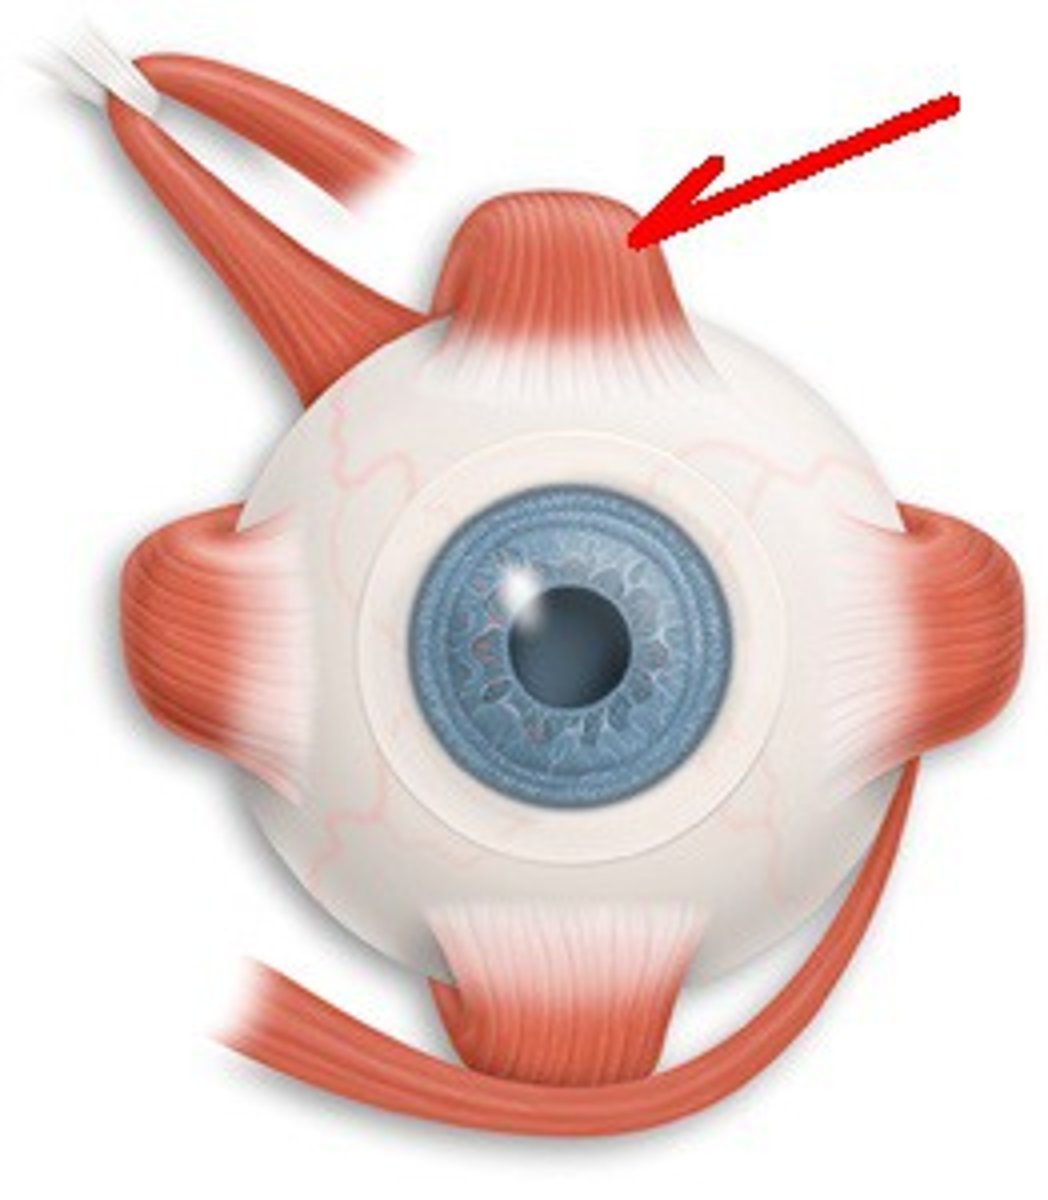

Superior Oblique

Inferior Oblique

Superior Rectus

Inferior Rectus

Lateral Rectus

Medial Rectus